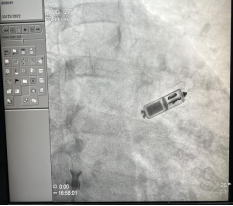

72岁的余阿姨近2年反复出现头昏、黑矇及晕厥,心电图发现窦性停搏,最慢心率40+次/分,且合并多年阵发性心房纤颤、高血压、糖尿病病史,心动过缓影响了余阿姨阵发性快速房颤的治疗,严重影响了余阿姨的生活质量,且潜在危及患者的生命,因此植入起搏器刻不容缓。但余阿姨具有高血压、冠心病、糖尿病等基础疾病,且患者不愿接受传统起搏器植入手术囊袋及电极的相关风险,我院心血管内科介入团队积极与患者充分沟通,决定选择最新一代Micra 无导线胶囊起搏器植入,经过周密的术前准备,三医院介入团队经右侧股静脉穿刺入路,顺利通过递送系统将起搏器送至患者右心室间隔部位,一次性释放成功固定良好,全程40分钟顺利完成手术。术后心率即刻稳定在60次/分以上,术后8小时即下地活动。 目前患者恢复良好。

无导线起搏器目前为世界上体积最小的起搏器,仅有维生素胶囊大小,重量仅约2克,兼容1.5T/3.0T全身核磁共振扫描检查,能智能感知心房信号,实现生理性的房室同步起搏。无导线起搏器直接将起搏器植入在心腔内,因无需静脉植入心内膜电极,从而避免了传统起搏器手术创口疤痕及囊袋痕迹,避免了电极脱位、断裂的风险及囊袋感染带来的灾难性后果,植入后几乎感觉不到起搏器的存在,上肢活动完全不受限制,生活质量显著提高。